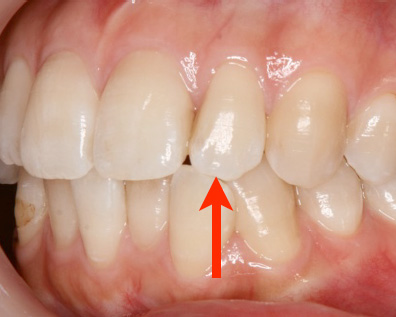

右の写真は矢印のところで強く当たっていました。その結

果、いつの間にか神経が死んで、根の先に病巣ができていま

す。幸い、痛みは自覚していませんでした。虫歯が原因であろ

うが、噛み合わせが原因であろうが、痛みは同じです。両方とも神経を取れ